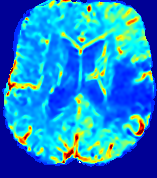

LesionRefer to captionRefer to captionRefer to captionRefer to captionRefer to captionRefer to caption𝐕rgbsubscript𝐕𝑟𝑔𝑏{\bf{V}}_{rgb}Refer to captionRefer to captionRefer to captionRefer to captionRefer to captionRefer to caption𝐕2subscriptnorm𝐕2{\|\bf{V}}\|_{2}Refer to captionRefer to captionRefer to captionRefer to captionRefer to captionRefer to captionRefer to caption3.53.53.52.82.82.82.12.12.11.41.41.40.70.70.70.00.00.0(mm/s)𝑚𝑚𝑠(mm/s)D𝐷DRefer to captionRefer to captionRefer to captionRefer to captionRefer to captionRefer to captionRefer to caption0.0200.0200.0200.0160.0160.0160.0120.0120.0120.0080.0080.0080.0040.0040.0040.0000.0000.000(mm2/s)𝑚superscript𝑚2𝑠(mm^{2}/s)Slice #1Slice #2Slice #3Slice #4Slice #5Slice #6

Figure 3: PIANO feature maps for one stroke patient, where the lesion is located in the left hemisphere. Top row: segmented stroke lesion region (white) on different slices, obtained from ISLES 2017. The corresponding slices for the PIANO feature maps are shown in the following rows.

For a better insight into an estimated velocity field 𝐕𝐕{\bf{V}} and diffusion field 𝐃𝐃{\bf{D}}, we compute the following maps: (1) 𝐕rgbsubscript𝐕𝑟𝑔𝑏{\bf{V}}_{rgb}: Color-coded orientation map of 𝐕=(Vx,Vy,Vz)T𝐕superscriptsuperscript𝑉𝑥superscript𝑉𝑦superscript𝑉𝑧𝑇{\bf{V}}=(V^{x},V^{y},V^{z})^{T}, obtained by normalizing 𝐕𝐕{\bf{V}} to unit length and mapping its 3 components to red, green, blue respectively; (2) 𝐕2subscriptnorm𝐕2\|{\bf{V}}\|_{2}: 222 norm of 𝐕𝐕{\bf{V}}; (3) D𝐷D: scalar field in Eq. 5.

Fig. 3 and Fig. 4 show the PIANO feature maps estimated from two ISLES 2017 patients: all are highly consistent with the lesion in both cases. Details of the blood flow trajectories are revealed in 𝐕rgbsubscript𝐕𝑟𝑔𝑏{\bf{V}}_{rgb} by the ridged patterns and the sharp changes of colors in the unaffected (right) hemisphere, while the flat patterns appearing within the lesion provide little directional information about the velocity and indicate low velocity magnitudes. Velocity magnitudes are more directly visualized via 𝐕2subscriptnorm𝐕2\|{\bf{V}}\|_{2}, from which one can easily locate the lesion where 𝐕2subscriptnorm𝐕2\|{\bf{V}}\|_{2} is low. D𝐷D also indicates lower diffusion values in the lesion, though with less contrast potentially due to the fact that it captures the accumulated effect of CA diffusion at the voxel-level.